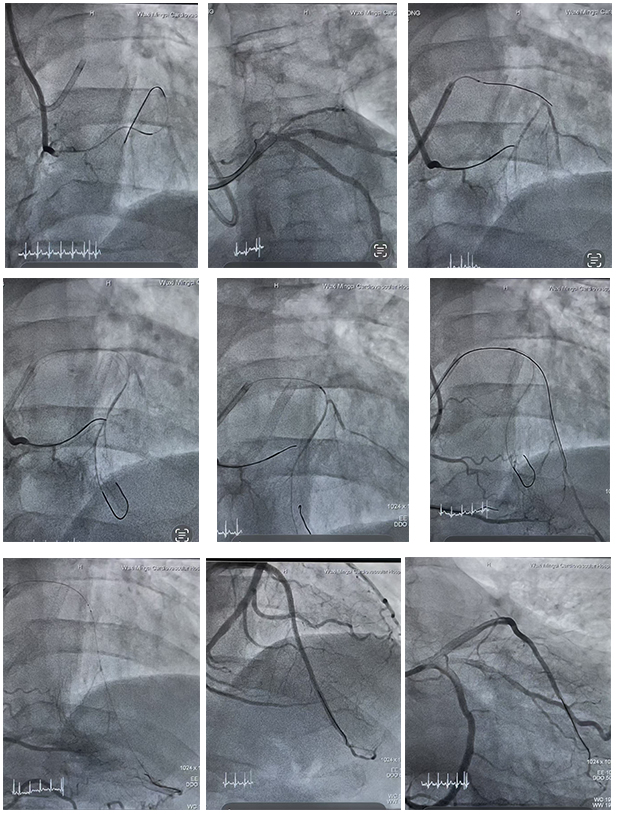

在医学界,冠状动脉慢性完全闭塞(CTO)因其介入治疗难度大、手术成功率低,被喻为冠脉介入领域“最后的堡垒”。而当患者同时面临右冠CTO和前降支开口无残端CTO

农历新年临近,48岁的无锡市民庄先生却因“缺血性心肌病”导致胸闷气喘急剧加重,夜间无法平卧,日常活动严重受限。庄先生身患慢性心功能不全、慢性肾功能不全(5期,

2026年1月28日,无锡明慈医院心脏中心在陈风主任的带领下,成功完成一例高难度复杂冠脉介入手术,为患者顺利置入了美敦力第六代Onyx药物洗脱支架。据悉,这是